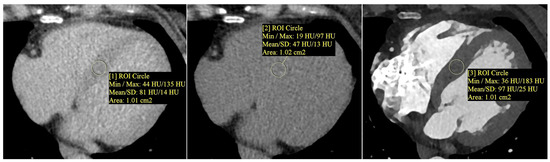

Myocardial extracellular volume (ECV) was calculated semi-automatically using the CT Cardiac Functional Analysis post-processing application (module version 3.0.1, running on syngo.via platform version VB60B_HF02; Siemens Healthineers AG, Forchheim, Germany)—Figure 2. The calculation was based on native and delayed phase images, and an ECV map of the left ventricle was generated, divided into 17 standard myocardial segments (LV). The final ECV value used for analysis represented the mean of all 17 segments (global myocardial ECV)—Figure 3.

Figure 2. Measurement of myocardial and blood pool attenuation (Hounsfield units, HU) was performed by placing circular regions of interest (ROIs, about 1.0 cm2) on native and delayed-phase cardiac CT images to quantify extracellular volume (ECV). From left to right: native (non-contrast) myocardium—ROI [1]; delayed-phase myocardium—ROI [2]; delayed-phase blood pool—ROI [3]. ROIs were positioned to avoid trabeculae, epicardial fat, and calcifications. Mean HU values ± SD are displayed. ECV was calculated using a standard formula that incorporates the patient’s hematocrit and the attenuation difference between the myocardium and blood pool. Note: ROI numbers [1], [2], and [3] refer to the image annotations and do not indicate literature references.